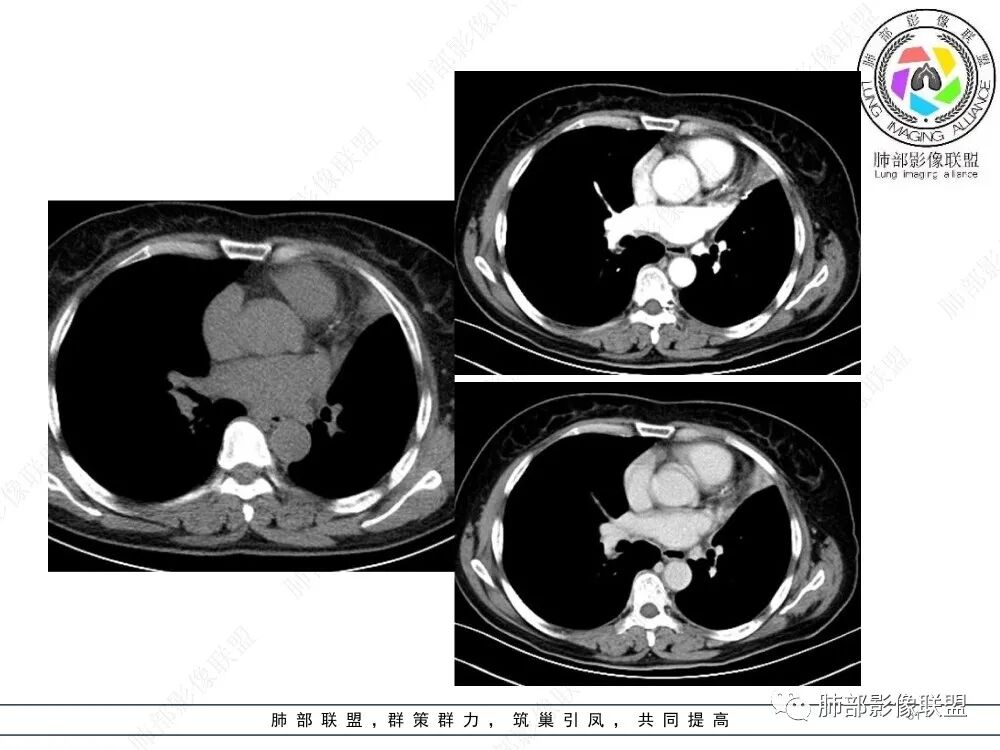

病灶腔内位主,局部膨隆凸向上叶支气管,两侧壁不清,病灶明显突出于壁外。

外形近端膨隆,远端收缩。

局部肺动脉受压明显,受压处似乎有点边界不清。

远端走形自然,提示远端不张,强化最明显处应该是单纯不张肺组织。

近端病灶内强化偏低,提示有侵犯。

综上,腔内占位明确,周围侵犯明确,支持支气管腔内恶性肿瘤,并阻塞性不张。